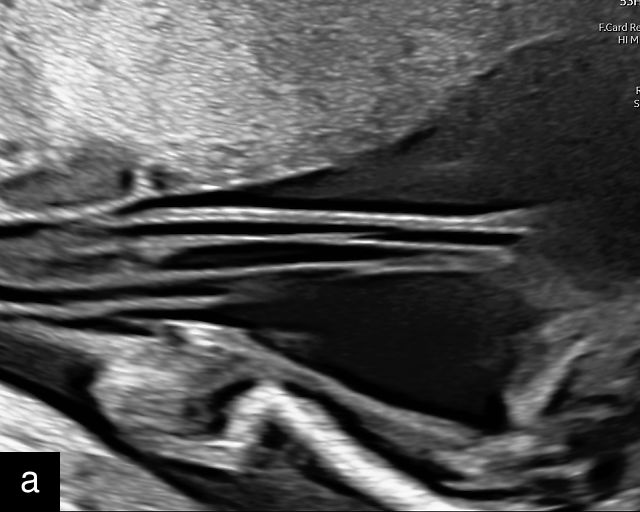

- The uterine wall (myometrium) and the decidua/chorion interface – The outermost layer, the uterine wall or myometrium, appears as a gray area with varying thickness (Figure 2a) depending on placental location. The myometrium is generally thicker when the placenta is located in the upper uterus or fundus. Just beneath the myometrium lies the decidua, a hypoechoic (black) layer where the spiral arteries develop.

- The umbilical cord insertion (Figure 2b,c) and placental margin (Figure 2d) – Special attention should be paid to the site at which the umbilical cord or vessels insert into the placenta, as well as the marginal regions of the placenta, to identify potential abnormalities.

2

(a) Transabdominal grayscale ultrasound image of the placenta showing the four key placental regions: the myometrium (gray area), decidua (black line), chorion (light gray thin line), placental body (p), and the chorion–amnion interface. (b) Grayscale ultrasound image of the umbilical cord insertion into the placenta. (c) Same view as in (b) but with color Doppler applied. (d) Normal placental edge (arrow), which is a common location for placental lakes. (e) Rolled placental edges (arrows) in circumvallate placenta (p).

Hernandez-Andrade and colleagues assert that most placental abnormalities can be accurately identified using gray-scale ultrasound alone, but color Doppler can be a valuable tool in distinguishing between certain lesions.2,15 By following this structured approach, these authors propose that the majority of placental and cord abnormalities can be effectively recognized, leading to improved diagnostic accuracy and better prenatal care.2